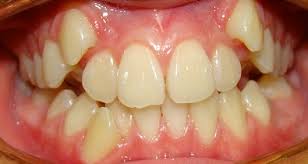

4. Răng mọc lệch: Phổ biến nhất là răng nanh hàm trên và răng khôn. Trong trường hợp răng khôn mọc lệch thì nhổ răng là cách duy nhất để ngăn chặn những tình huống xấu hơn có thể xảy ra.

Chỉnh hình răng: Đôi khi cần nhổ răng để tạo những khoảng trống cần thiết cho điều trị chỉnh hình răng.

Răng mọc lệch   Răng chỉnh hình             Răng bị chấn thương